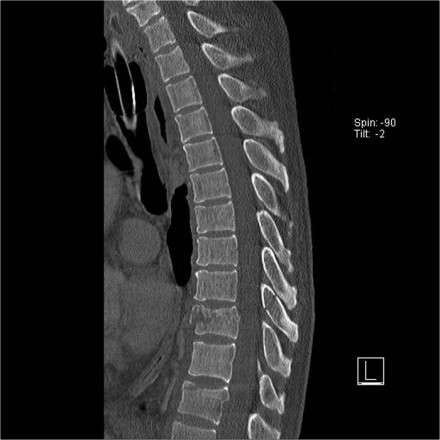

Patients with a rigid spine (such as in ankylosing spondylitis, DISH and rheumatoid arthritis) are more susceptible to spinal fractures, even after minimal trauma (6).

Ossification of the spinal ligaments and calcification of the annulus fibrosus alter the biomechanics of the spine, creating long lever arms and limiting the ability to absorb even minor impacts.

The bone is usually very osteoporotic.

The images are of a patient with a typical bamboo spine as a result of ankylosing spondylitis.

After a fall on his back no fracture was seen on the x-rays.

However the CT shows a thin fracture line through the anterior side of the vertebral body and also through the spinous process.